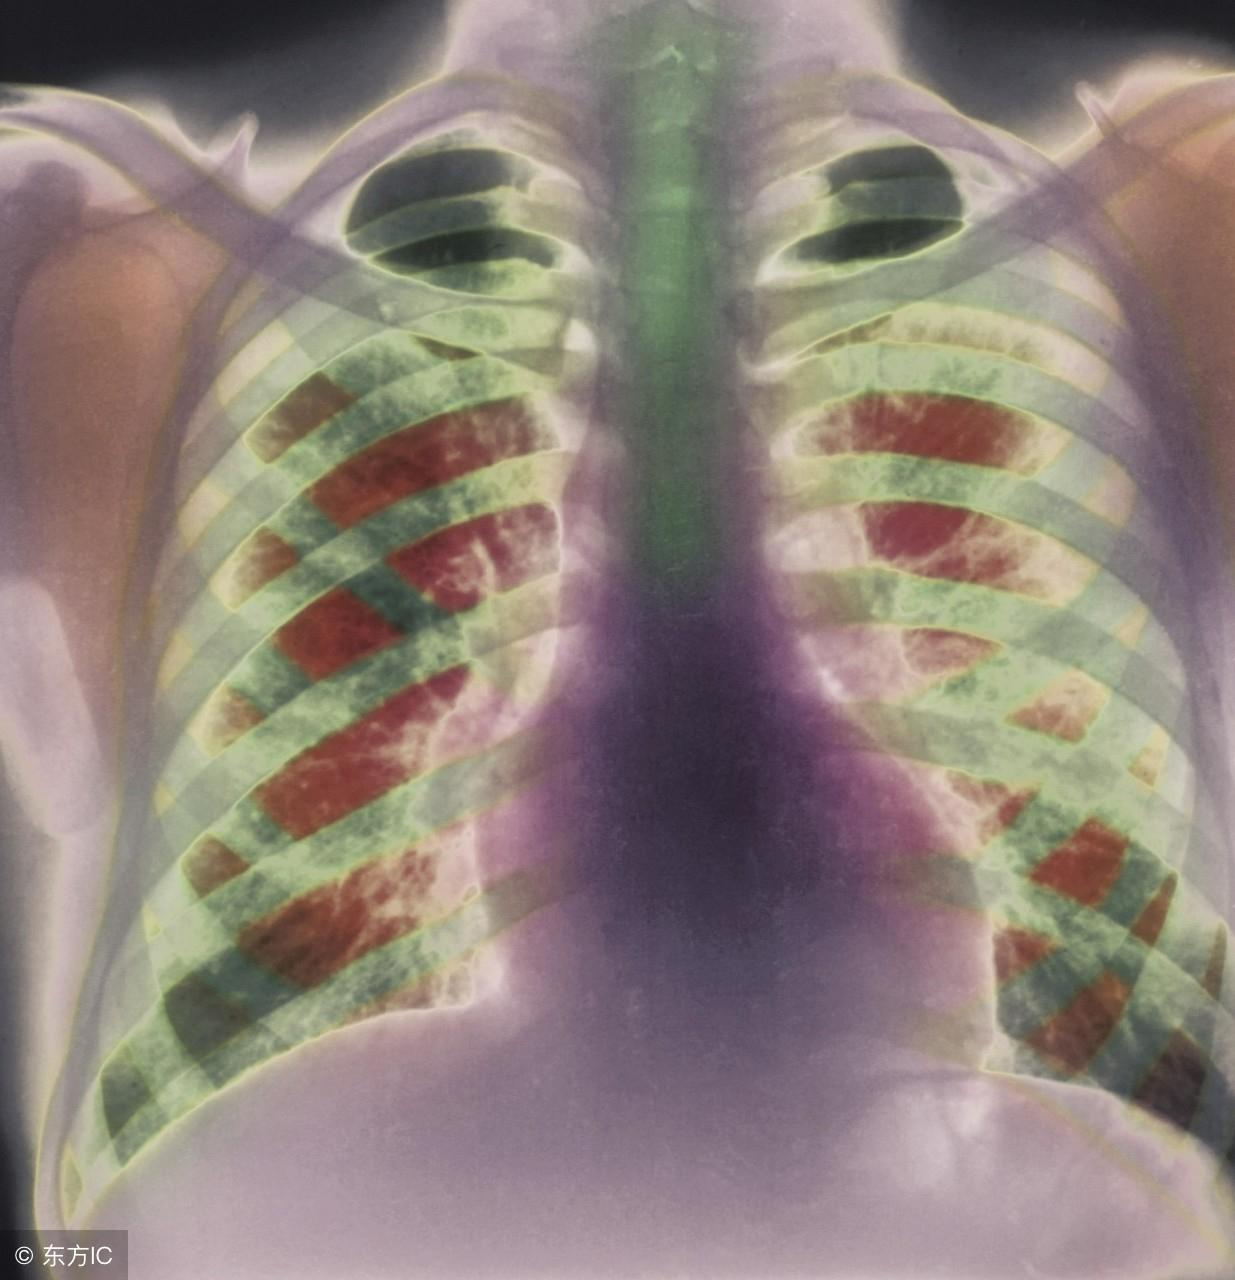

喝尿能治肺气肿?

而且,肺气肿是一种不可逆的损伤,指气道弹性减退,肺泡充气,过度膨胀导致肺容积增大,同时伴有气道壁破坏。一旦患上,只能通过治疗来减缓其发展或是缓解症状。不少人因此过早地丧失劳动能力,并且长期咳喘让人痛苦万分,很多人因此对病症悲观失望,于是乱用偏方。其实,如能进行规范化治疗,配合锻炼运动,是可以明显改善症状的。